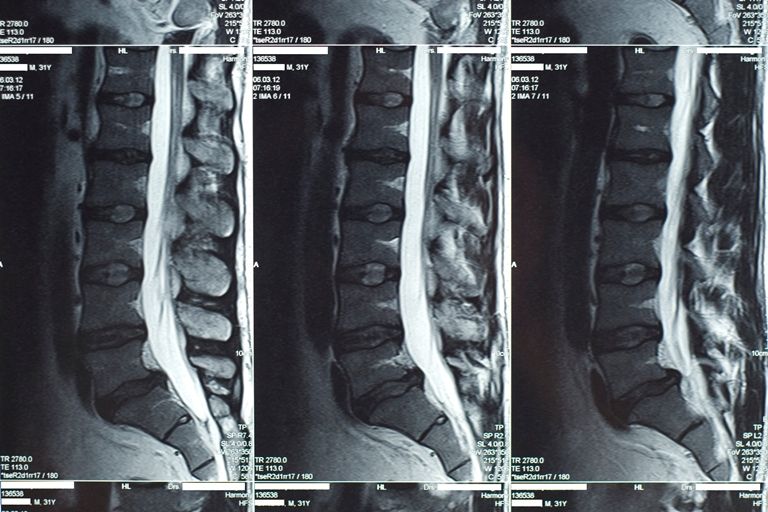

В настоящее время сложились определенные направления использования МТР в медицине. Так, функциональная МРТ позволяет определять индивидуальное местоположение и особенности областей мозга, отвечающих за движение, речь, зрение, память и другие функции человека. Магнитно-резонансная ангиография позволяет изучать просвет кровеносных сосудов головного мозга. МРТ позвоночника применяется нейрохирургами для определения грыж межпозвонковых дисков и степени нестабильности позвоночника (рис.5).